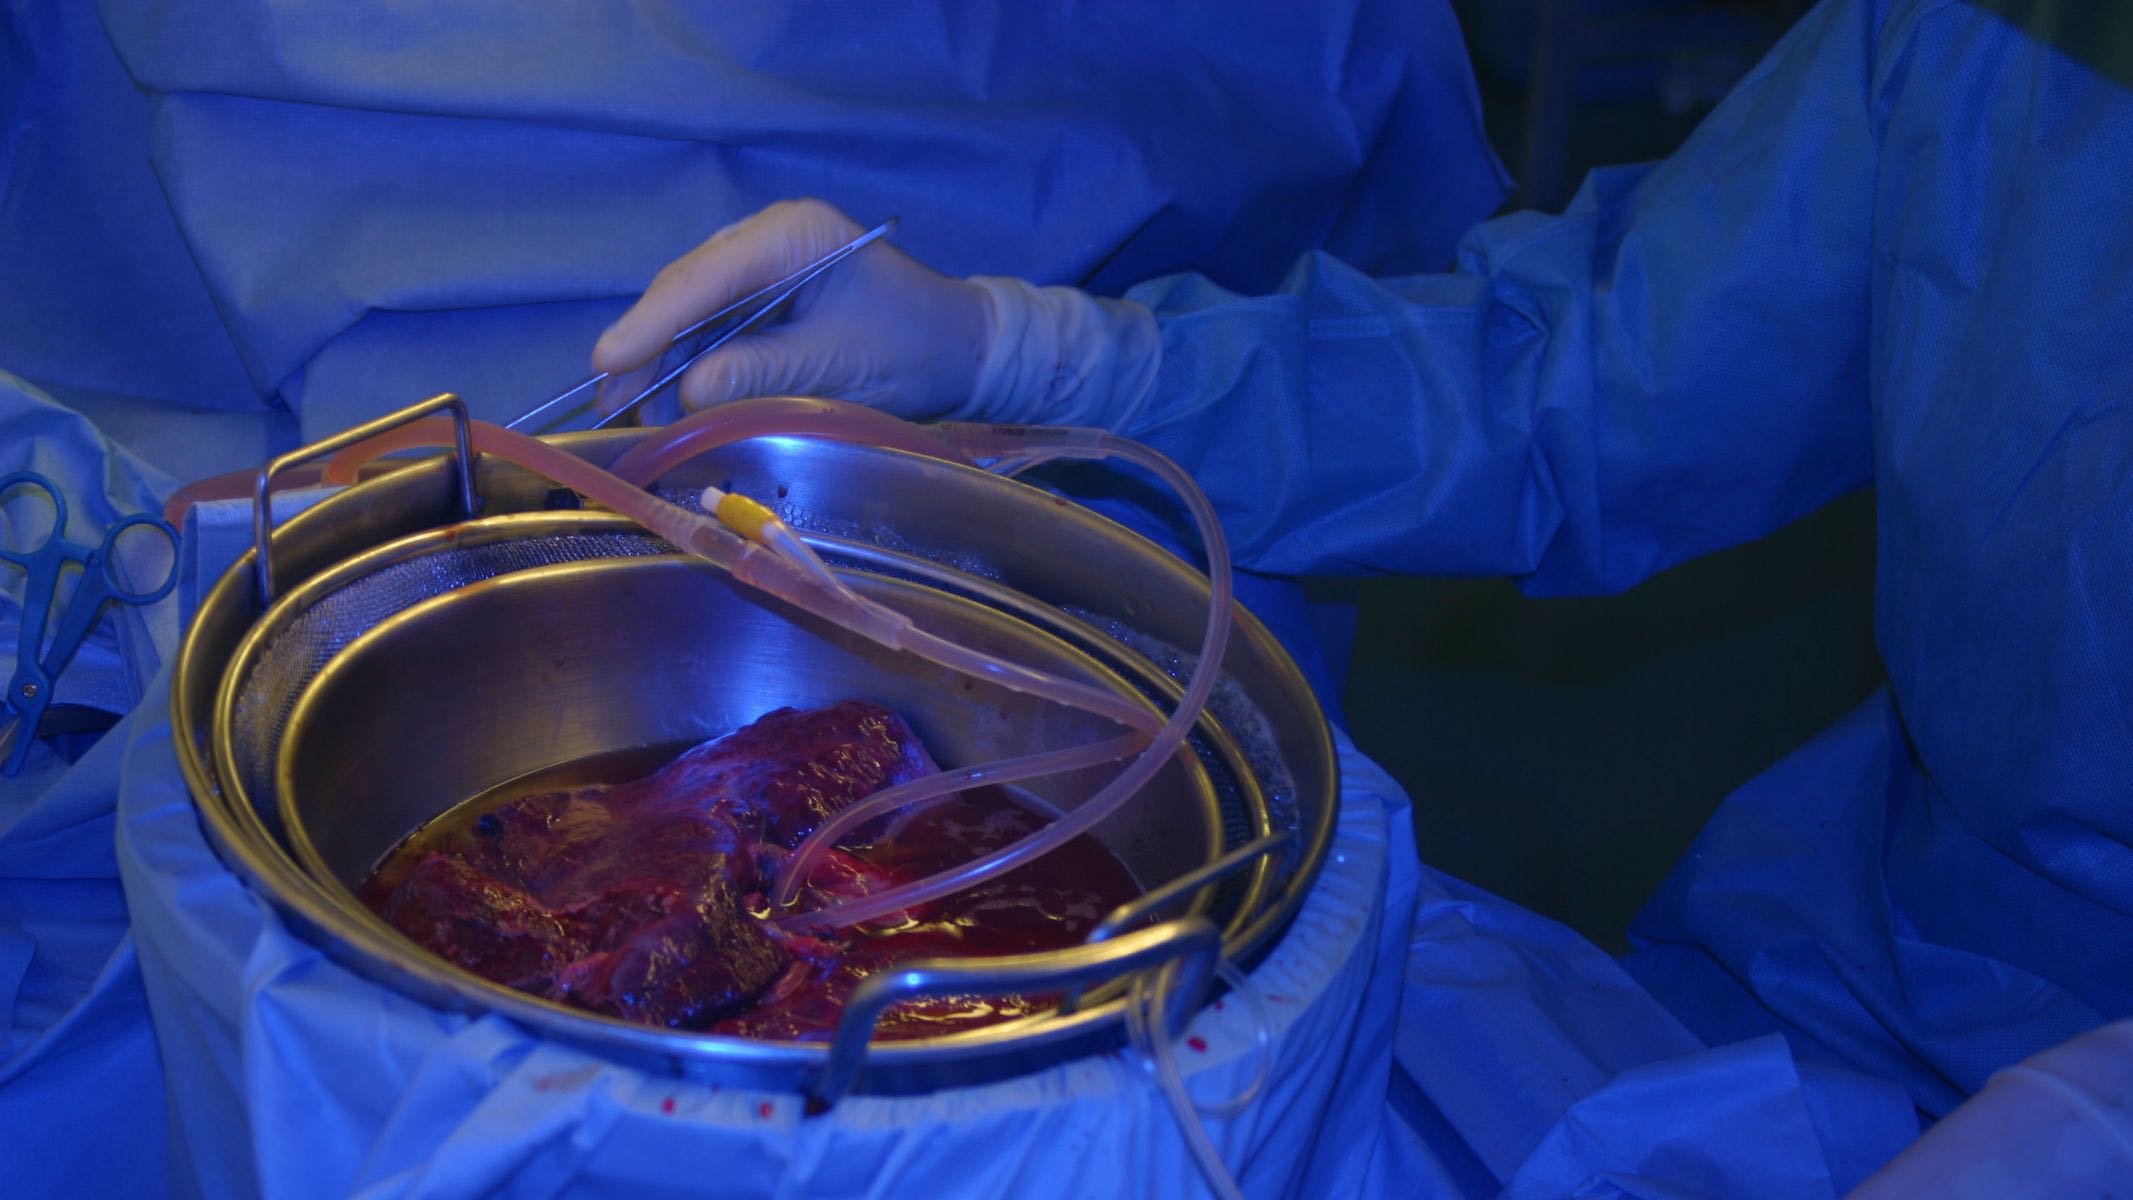

The Charité is one of the leading Transplantation Centers in Germany. The department of Surgery, Campus Charité Mitte | Campus Virchow - Klinikum (head: Prof. Dr. J. Pratschke) offers kidney, liver, pancreas and multiple organ transplantion. Beside a broad portfolio of clinical trials in transplantation the experimental research program consists of an interactive group of basic and clinical investigators from the departments of Immunology, Nephrology and Surgery.

Organ Recovery